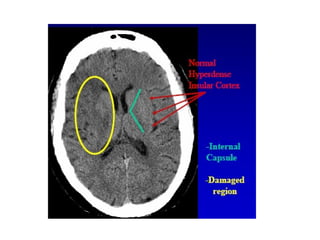

**This figure shows :

-The insular cortex is located along the Sylvian fissure

overlying the external capsule where a ribbon of

normal cortex should be appreciable (red arrows)

-In the setting of MCA infarction , cytotoxic edema leads

to hypoattenuation such that the normal insular

ribbon is no longer visible (blue arrows)

-The left image shows a very early infarct (within the first

few hours) while the right image shows a more

established infarct (greater than 4 hours old)